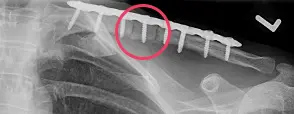

- Der Marknagel kann – je nach knöcherner Heilung – nach frühestens 3 Monaten wieder entfernt werden. Die Platten, welche doch oftmals etwas auftragen und stören, werden in aller Regel frühestens nach einem Jahr entfernt. Eine zu frühe Metallentfernung birgt das Risiko einer Re-Fraktur (siehe Abbildung), d.h. eines erneuten Schlüsselbeinbruchs.

Abbildung: Zweite Episode einer Re-Fraktur bei einer jungen Patientin. Daher Revision mit langer Platte und zudem Einsetzen eines Beckenkammspans (rot markiert) post-OP und das Ausheilungsergebnis 1 Jahr nach der OP